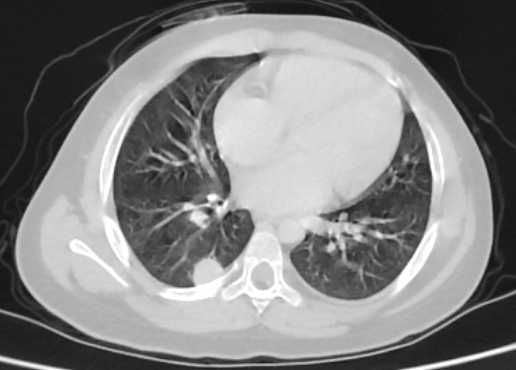

Abdominal ultrasound showed a heterogenous left supra renal mass with multiple liver lesions. Chest and abdominal CT scan showed a 14.2cmx6.4cm well-defined heterogeneously enhanced left suprarenal mass with internal areas of chunky calcification and necrosis. The mass extended down anterior to the left kidney abutting the renal pedicle with no invasion or thrombus. It had pushed the left kidney inferiorly and posteriorly. The liver showed multiple large heterogeneously enhancing lesions with internal necrotic areas. There were also multiple peripheral nodules in the bilateral lung bases (Figure 2).

Figure 2: Coronal and sagittal reformatted contrast-enhanced CT image (A and B) shows large heterogeneously enhanced left suprarenal mass with calcification (black arrow). Note the liver metastasis in (white arrow in A). Axial CT image of the lung (C) demonstrates a peripherally located metastatic lesion in the right lung (white arrow). Axial contrast-enhanced CT image (D) shows a heterogenous left suprarenal mass (asterisk) with liver metastasis (white arrow).